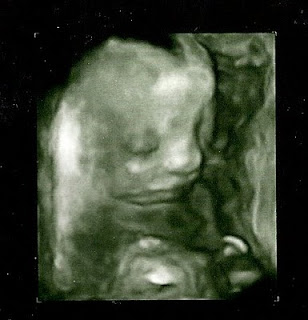

The tech we had was wonderful and so very nice. She kept playing with the baby and saying how cute he or she was! JuneBug was a bit rambunctious and was having a jolly time flipping all about. Yet, the tech was able to get all of the pictures she needed in order to tell us that the bug was looking just right! There was one point where she said she was going "down there" if we wanted to know the sex and for a split second I looked at Billy and we were about to cave, but somehow I mustered up the courage to avoid the temptation and I looked away and said no! Afterwards the heart doctor met us in his office and went over the results as well saying that the heart looked great and the blood was flowing through the chambers just fine! It was such a wonderful appointment and looking at the pictures.. I just think they are sooo very cool! I have never had pictures of either of my girls in the utero like this and I cant help but notice that this bug looks so very much like Miss Layla! Ahhh only 19 more weeks and the identity will be revealed!